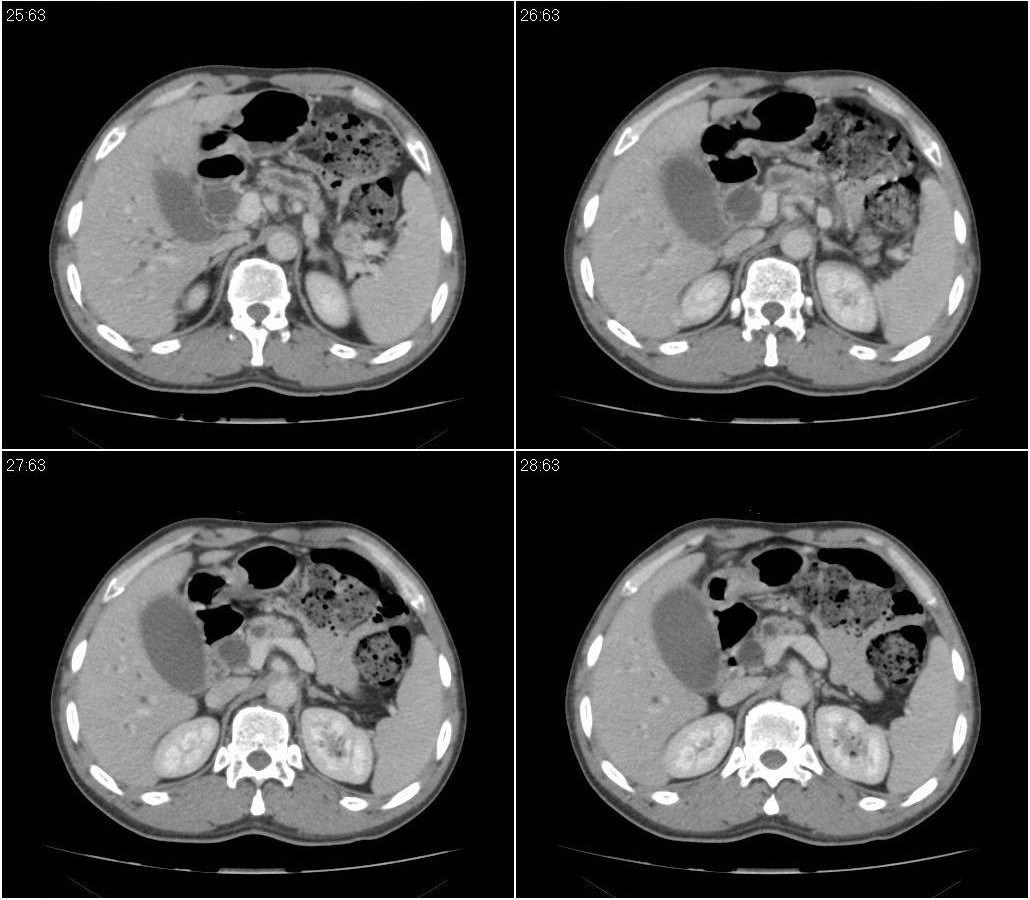

标题: CT21384:男性,50岁。发现无痛性黄疸十余天,B朝提示肝胆管 [打印本页]

标题: CT21384:男性,50岁。发现无痛性黄疸十余天,B朝提示肝胆管

1.考虑:壶腹占位病变(癌?)。

2.胆系低位梗阻:肝内外胆管扩张,胆囊增大,胰管扩张。

胆系低位梗阻(肝内外胆管扩张,胆囊增大,胰管扩张);考虑胰头癌或壶腹癌所致。

胆总管突然中断,壁增厚且强化,考虑胆总管癌可能性大伴胆系梗阻,胆囊炎

胰头强化欠均匀,胆胰管扩张。考虑胰头癌可能性大。

胆系低位梗阻(肝内外胆管扩张,胆囊增大,胰管扩张,钩突似有占位);考虑胰头癌